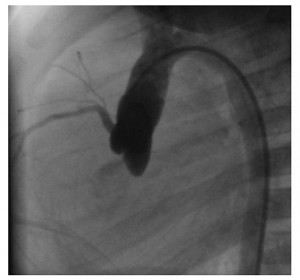

Ecocardiografia a depistat o malformaţie cardiacă congenitală simplă: defect septal interatrial (DSA) larg, tip ostium secundum, cavităţi drepte mult dilatate (atriu drept, ventricul drept, artera pulmonară), hipertensiune pulmonară (presiune pulmonară medie: 40 mmHg), defect septal interventricular muscular apical mic, insuficienţă mitrală uşoară (Figura 1, 2).

Figura 1. Ecocardiografie transtoracică incidenţă apical 4 camere: dilataţie de cavităţi drepte, defect septal interatrial tip ostium secundum. AD: atriu drept, VD: ventricul drept, AS: atriu stâng, VS: ventricul stâng.